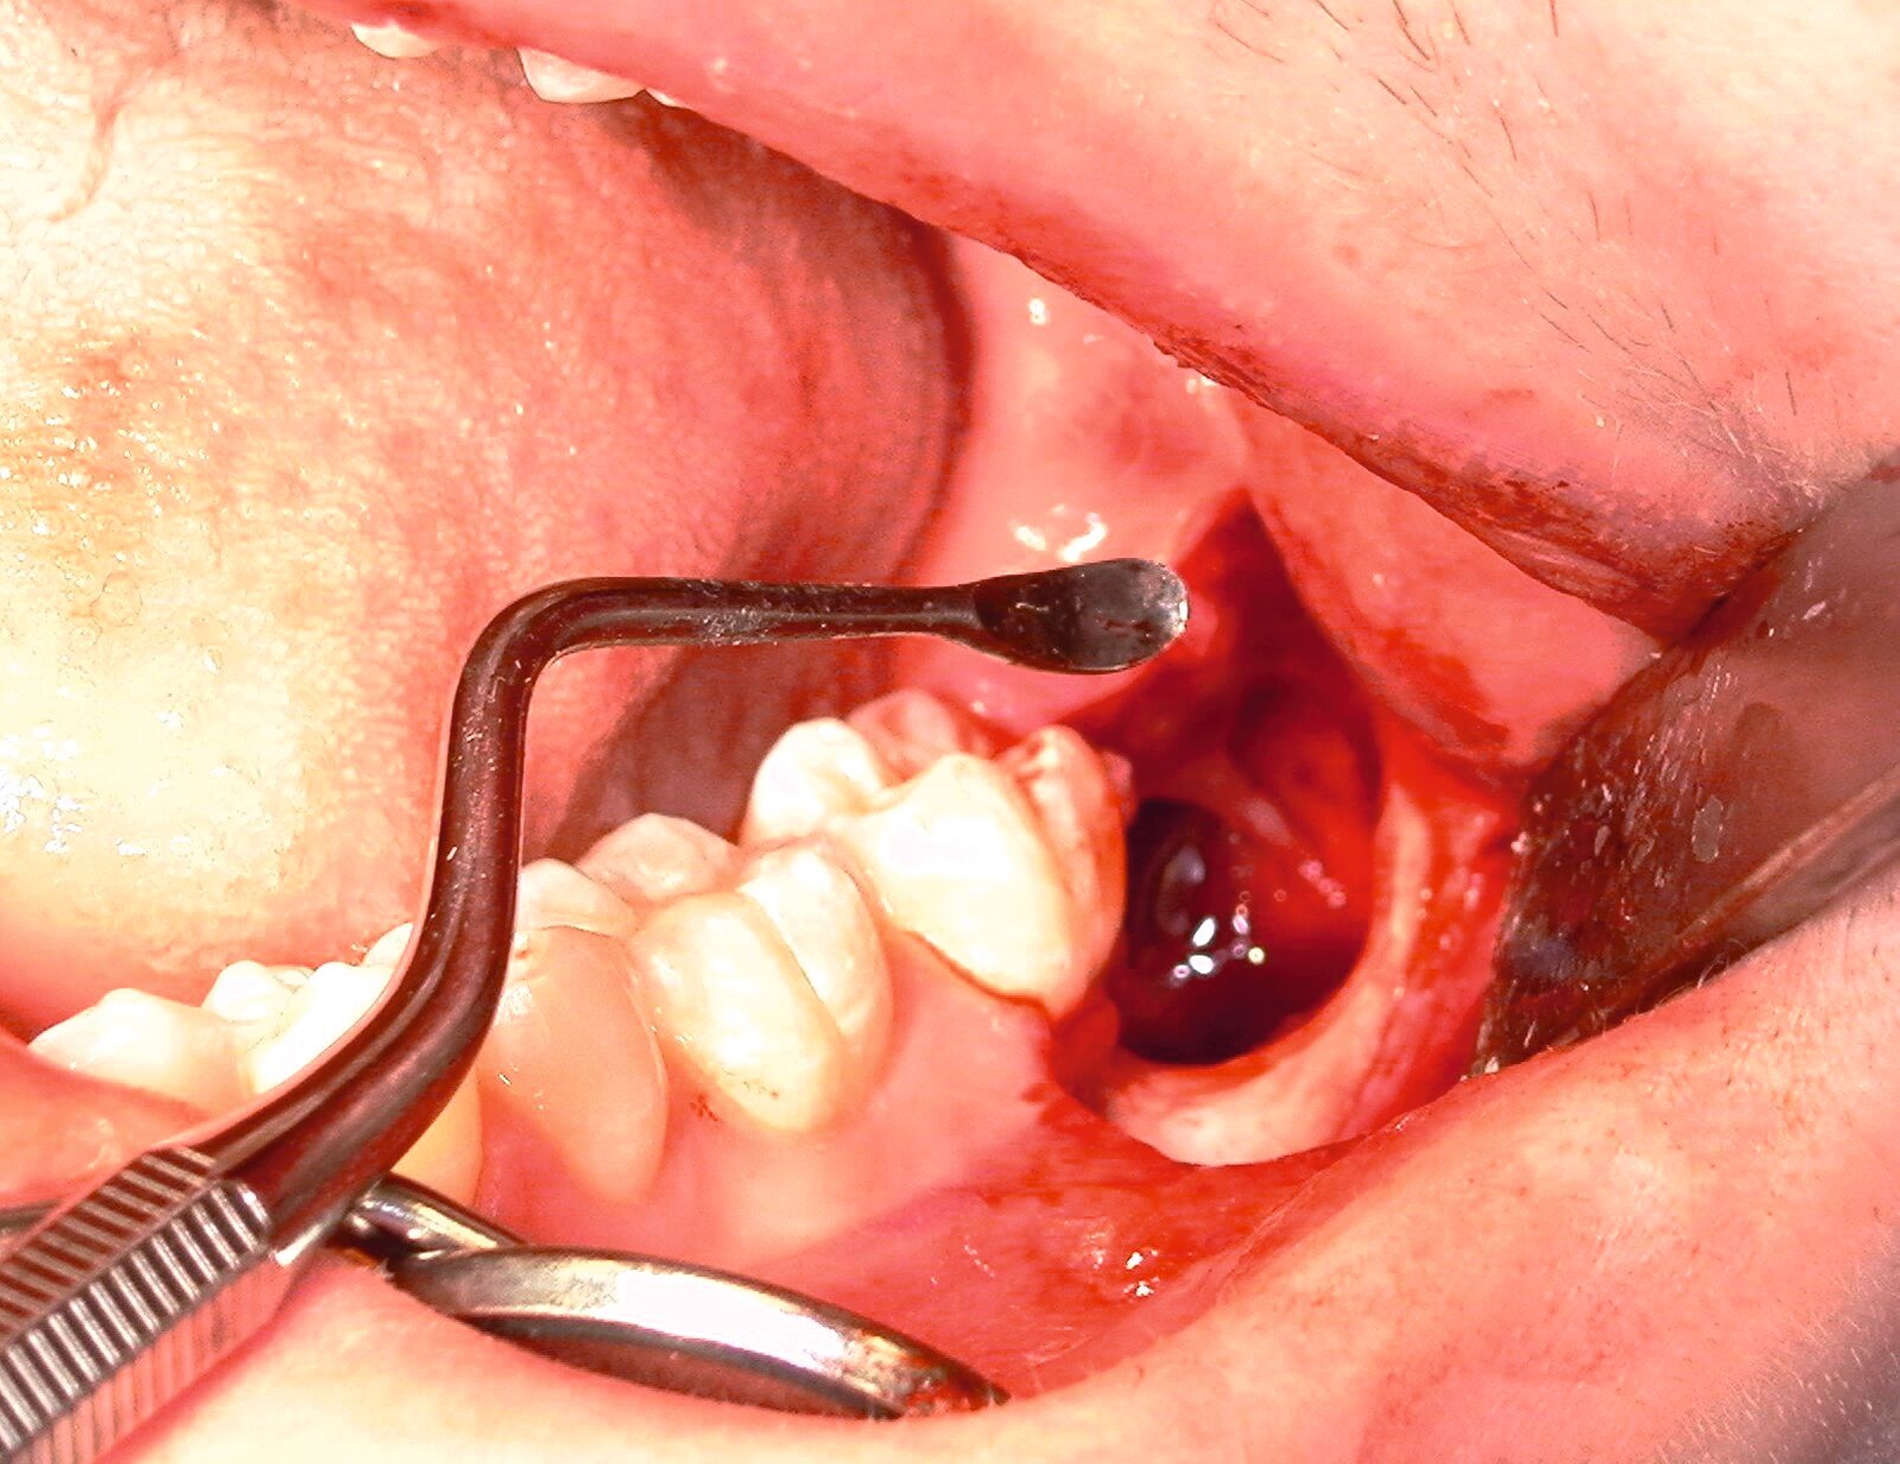

Nach Freilegung des Knochens kann ein Wundhaken nach Langenbeck eingesetzt werden sowie ein Bohr-Raspatorium zum Schutz des N. lingualis subperiostal lingual [Gutwald et al., 2019]. Unter Verwendung eines rotierenden Instruments (Kugel- und Lindemann-Fräse) oder Piezochirurgie wird der Knochen im Bereich der Zahnkrone abgetragen und diese freigelegt (Abbildung 8). Danach kann der Weisheitszahn vorsichtig mithilfe eines Bein‘schen Hebels anluxiert oder, falls dies noch nicht gelingt, mittels einer Lindemann-Fräse geteilt werden. Dabei wird am größten Kronendurchmesser die Krone mit der Fräse abgetrennt und die Wurzel anschließend separat entfernt (Abbildungen 9 und 10) [Gutwald et al., 2019; Schwenzer, 2019].

Anschließend erfolgt die sorgfältige Kürettage unter Schutz des am Boden der Extraktionsalveole liegenden Canalis mandibularis, die Entfernung von Granulationsgewebe sowie des Follikelepithels. Die Wurzelspitze sollte auf Vollständigkeit überprüft werden, um eine Wurzelfraktur auszuschließen (Abbildung 11).